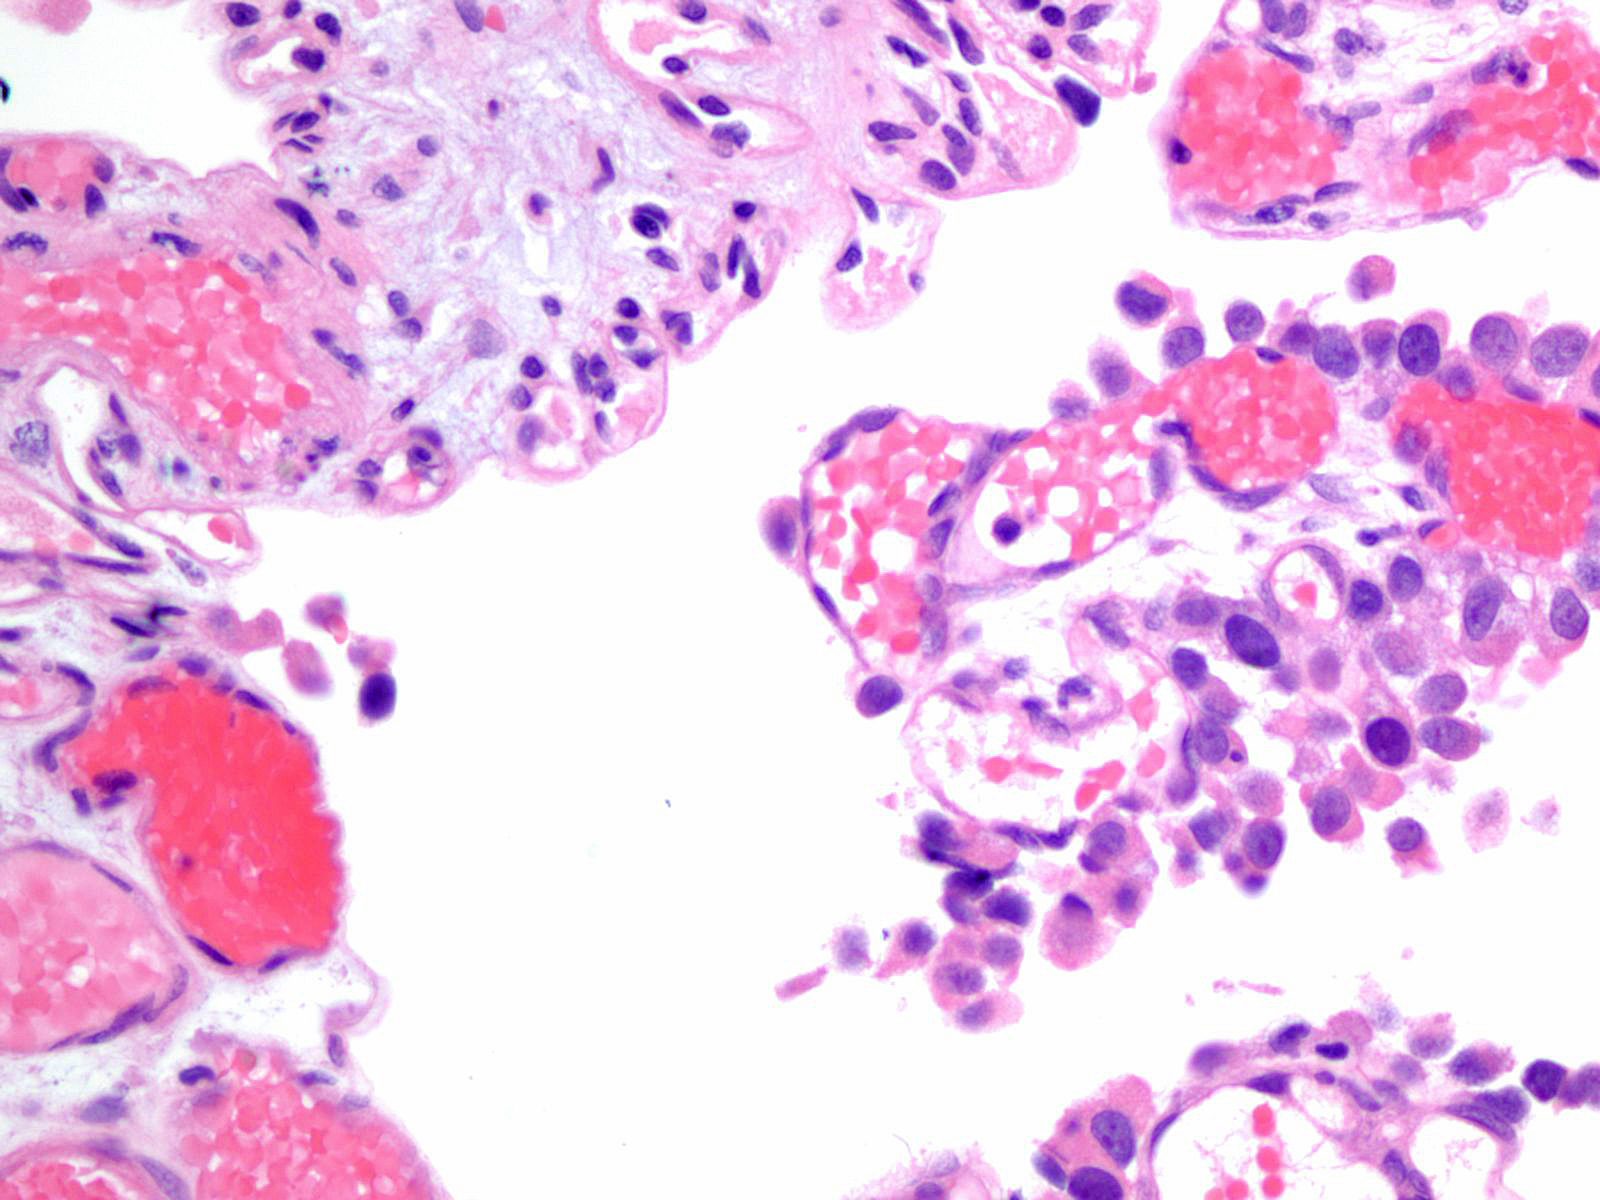

Consensus grade: High-grade papillary urothelial carcinoma (HG-PUC)

Case description (by case creator):

Lesion shows marked denudation. The cells lining the papillary fronds depict marked variation in nuclear size, shape and chromatin. Cells appear loosely cohesive and the architecture is disorganized.